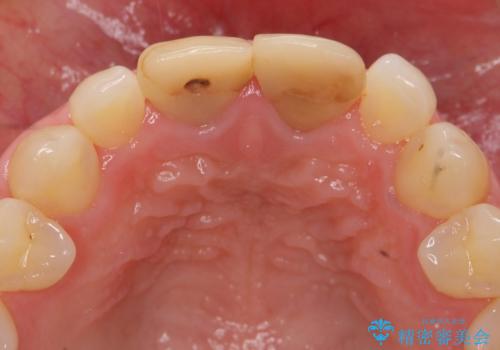

- 32万円(仮歯・ファイバーコア・ジルコニアクラウンスペシャル×2)費用は治療当時の料金となります

ただ見えるクラウンを白くきれいにするのではなく、長期的な歯の予後を考えると根管治療・ファイバーコア築盛・精密な歯牙形成等クリアすべき条件は多々あると言えます。